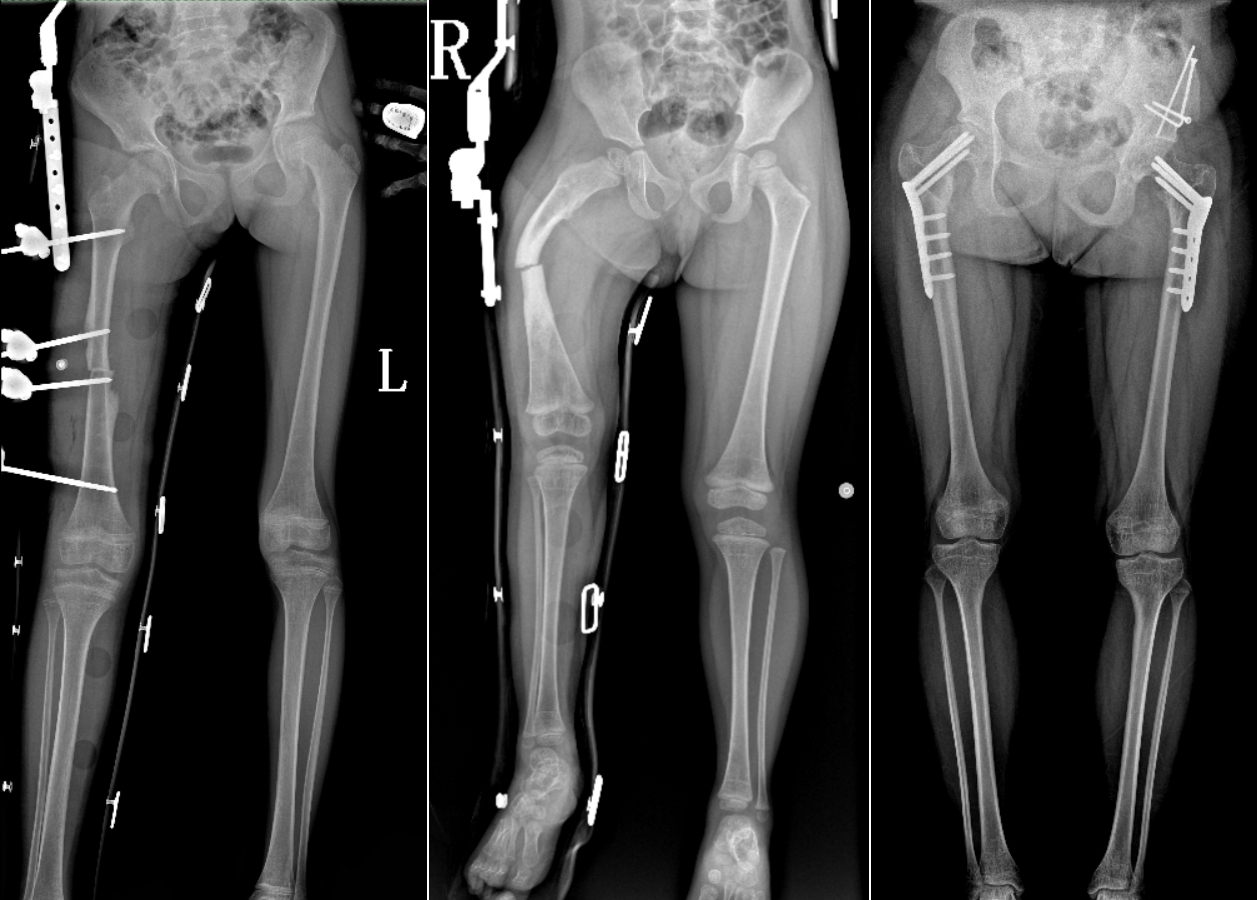

DR是臨床骨科的重要檢查手段之一。在骨科檢查中,脊柱矯形、長骨骨折、腰椎退行性病變等,需要采集脊柱、下肢全景圖像,輔助醫(yī)生臨床診斷,從而制定科學(xué)的治療方案,普愛醫(yī)療的大視野平板動(dòng)態(tài)DR就像是一座橋梁,連接起現(xiàn)代醫(yī)療技術(shù)與當(dāng)?shù)厝嗣竦尼t(yī)療需求。

普愛醫(yī)療自主研發(fā)的大視野平板動(dòng)態(tài),采用17"*34"的有效視野,一次曝光即可得到全脊柱或全下肢影像。相較于多張攝影再軟件拼接的DR設(shè)備,PLX8600解決了拼接圖像存在密度不均勻,拼接處圖像配準(zhǔn)和放大效應(yīng)等問題,給臨床帶來了真正的大視野影像解決方案。

除了常規(guī)靜態(tài)攝影外,PLX8600的大平板具備動(dòng)態(tài)透視和點(diǎn)片功能,能夠很好地觀察復(fù)雜部位病灶,有效地抓取關(guān)鍵幀,降低患者多次攝片的概率。如:全脊柱狀態(tài)評(píng)估、長骨關(guān)節(jié)活動(dòng)度、下肢靜脈造影瓣膜功能評(píng)估、消化道功能評(píng)估、脊髓造影等更多大視野臨床應(yīng)用,“多面手”都能輕松應(yīng)對(duì)。